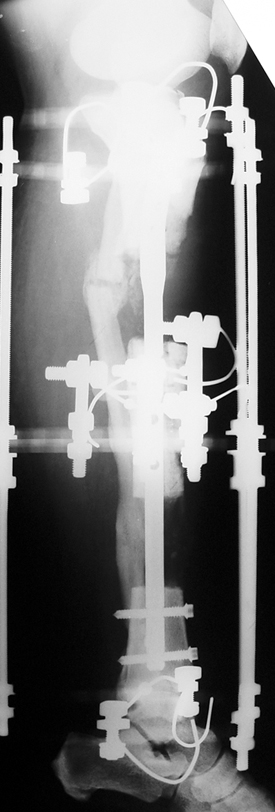

Uygun radikal debridman tüm nekrotik kemik ve yumuşak dokuların çıkartılmasını gerektirir, ve sıklıkla uzuvda instabiliteye neden olur. Kalan kemik ve yumuşak doku defektinin bir şekilde fiksasyonu ve rekonstrüksiyonu gereklidir. İlizarov’un ortaya koyduğu distraksiyon osteogenezi yöntemi, kaynamanın elde edilmesi, deformitenin düzeltilmesi, bacak boy eşitsizliğinin giderilmesi ve segmental defektlerin rekonstrükte edilmesi için başarıyla kullanılmaktadır.

Eksternal fiksatör ile geçen süre (eksternal fiksasyon indeksi), gereken distraksiyon miktarına bağlıdır ve bu süre boyunca bazı komplikasyonlarla karşılaşılabilir. Distraksiyon dönemi sona erdikten sonra, distraksiyon süresinin iki katını aşan konsolidasyon döneminde hastalar eksternal fiksatörü zorlukla tolere edebilirler. Yeterli konsolidasyon sağlanmadan eksternal fiksatör çıkartılırsa ise kırıklar, deformite ve kısalık oluşabilir. Hastanın fiksatör ile birlikte geçirdiği sürenin azaltılması ve böylece hasta konforunun ve aktivite düzeyinin arttırılması için intramedüller çivi üzerinden uzatma yöntemi uygulanmaktadır. Bu yöntemde distraksiyon dönemi sona erdiğinde kemiğin içindeki çivi statik olarak kilitlenmekte ve eksternal fiksatör çıkartılmaktadır. Stabilizasyon intramedüller çivi tarafından sağlandıktan sonra konsolidasyon dönemi gerçekleşmektedir. Bu şekilde hem eksternal fiksatörün uzun süre kalmasından hem de erken çıkartılmasından kaynaklanan komplikasyonların önüne geçilmektedir.